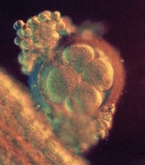

"Вече няма съмнение в истинността на тестовете. Иначе вие си живеете обичайния си живот, работите, забавлявате се, почивате си, правите секс, празнувате... Но организмът ви може би ви загатва за промените, произтичащи вътре в него - лека болка в гърдите, непоносимост към любими лакомства. Само за 7 дни една яйцеклетка се превръща в кълбо от стотици клетки! Но даже под микроскоп е трудно да се разбере по какви закони се ръководи това тайнство в организма на майката; кои клетки се превращат в „матрица“ на ембриона и кои са „назначени“ да отговарят за функционирането му. |

Образува се „бластоцистата“ - пълен с течност зародишен мехур от клетки. Повърхността му е покрита с власинки, а сърцевината с клетките на ембриона.

Той се прикрепя към вътрешната страна на матката с помощта на власинките и започва да черпи хранителни вещества от майчиния организъм. До този момент е ползвал собствените си ресурси.

Лигавицата на матката нараства и го покрива изцяло: образува се плацентата - орган, който ще храни и защитава детето през цялата бременност.

Бебето в момента е по-малко от половин милиметър в диаметър, но вече има дихателни кухини; тръбичка, която по-късно ще се превърне в сърце и специални клетки - основа на нервната система. "